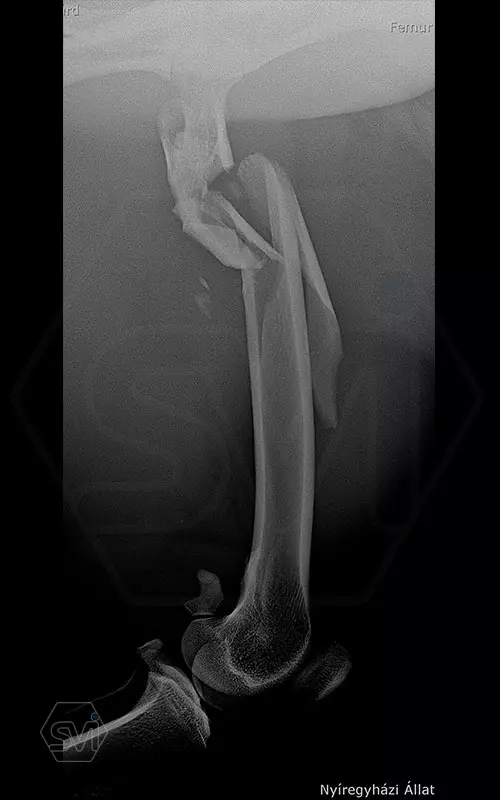

The 9-year-old female cheetah broke her leg so miserably near the femoral neck during a regrouping. Here again, the combination of the intramedullary pin and polyaxial lockin plate mentioned in the previous post was used to fix the fracture. During the screw insertions into the proximal piece, the polyaxiality came in really handy, we were able to avoid the 2.5 mm K-nails with the long screws. I hope the 14-hole 12 * 4 mm wide polyaxial plate (which could have been longer…) will be long enough, with a mix of 4.0 and 3.5 mm screws for maximum stability. From below, screw 6 is a cortical screw that secures a larger contralateral fragment as a lag screw.